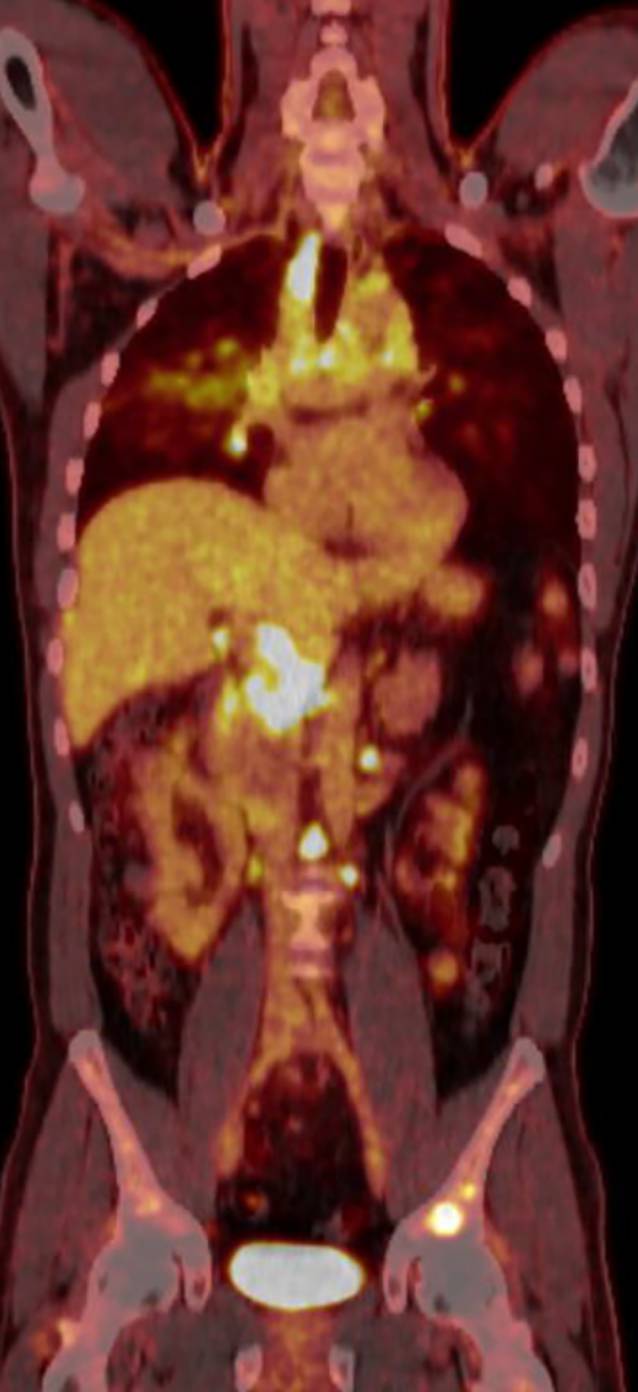

Vorwegzunehmen ist, dass die sichere Diagnose der Sarkoidose einen histologischen Nachweis der granulomatösen Entzündung und den Ausschluss anderer Ursachen von Granulomen, beispielsweise Tuberkulose oder Vaskulitiden, erfordert. Hilfreich dabei ist die Bildgebung: Während die Thoraxröntgenuntersuchung zwar durch die mediastinale und hiläre Lymphadenopathie und Parenchymveränderungen (Abb. 2) auffällig sein kann, ist die Computertomographie des Thorax (CT) wesentlich genauer und kann auch geringere Krankheitsausprägungen sicher detektieren (Abb. 3). Die 18F‑FDG-PET/CT hat sich weiters bewährt, extrathorakalen Befall darzustellen, geeignete Biopsiestellen zu identifizieren und in komplexen Fällen das Krankheitsansprechen zu kontrollieren (Abb. 4).

Abb. 4

Schnitt aus einer 18F‑FDG-PET/CT bei Sarkoidose mit Multiorganbefall. Neben metabolisch aktiver mediastinaler und hilärer Lymphadenopathie und Läsionen im Lungenparenchym bestehen auch abdominell auffällige Lymphknotenpakete sowie Knochenherde wie im linken Becken